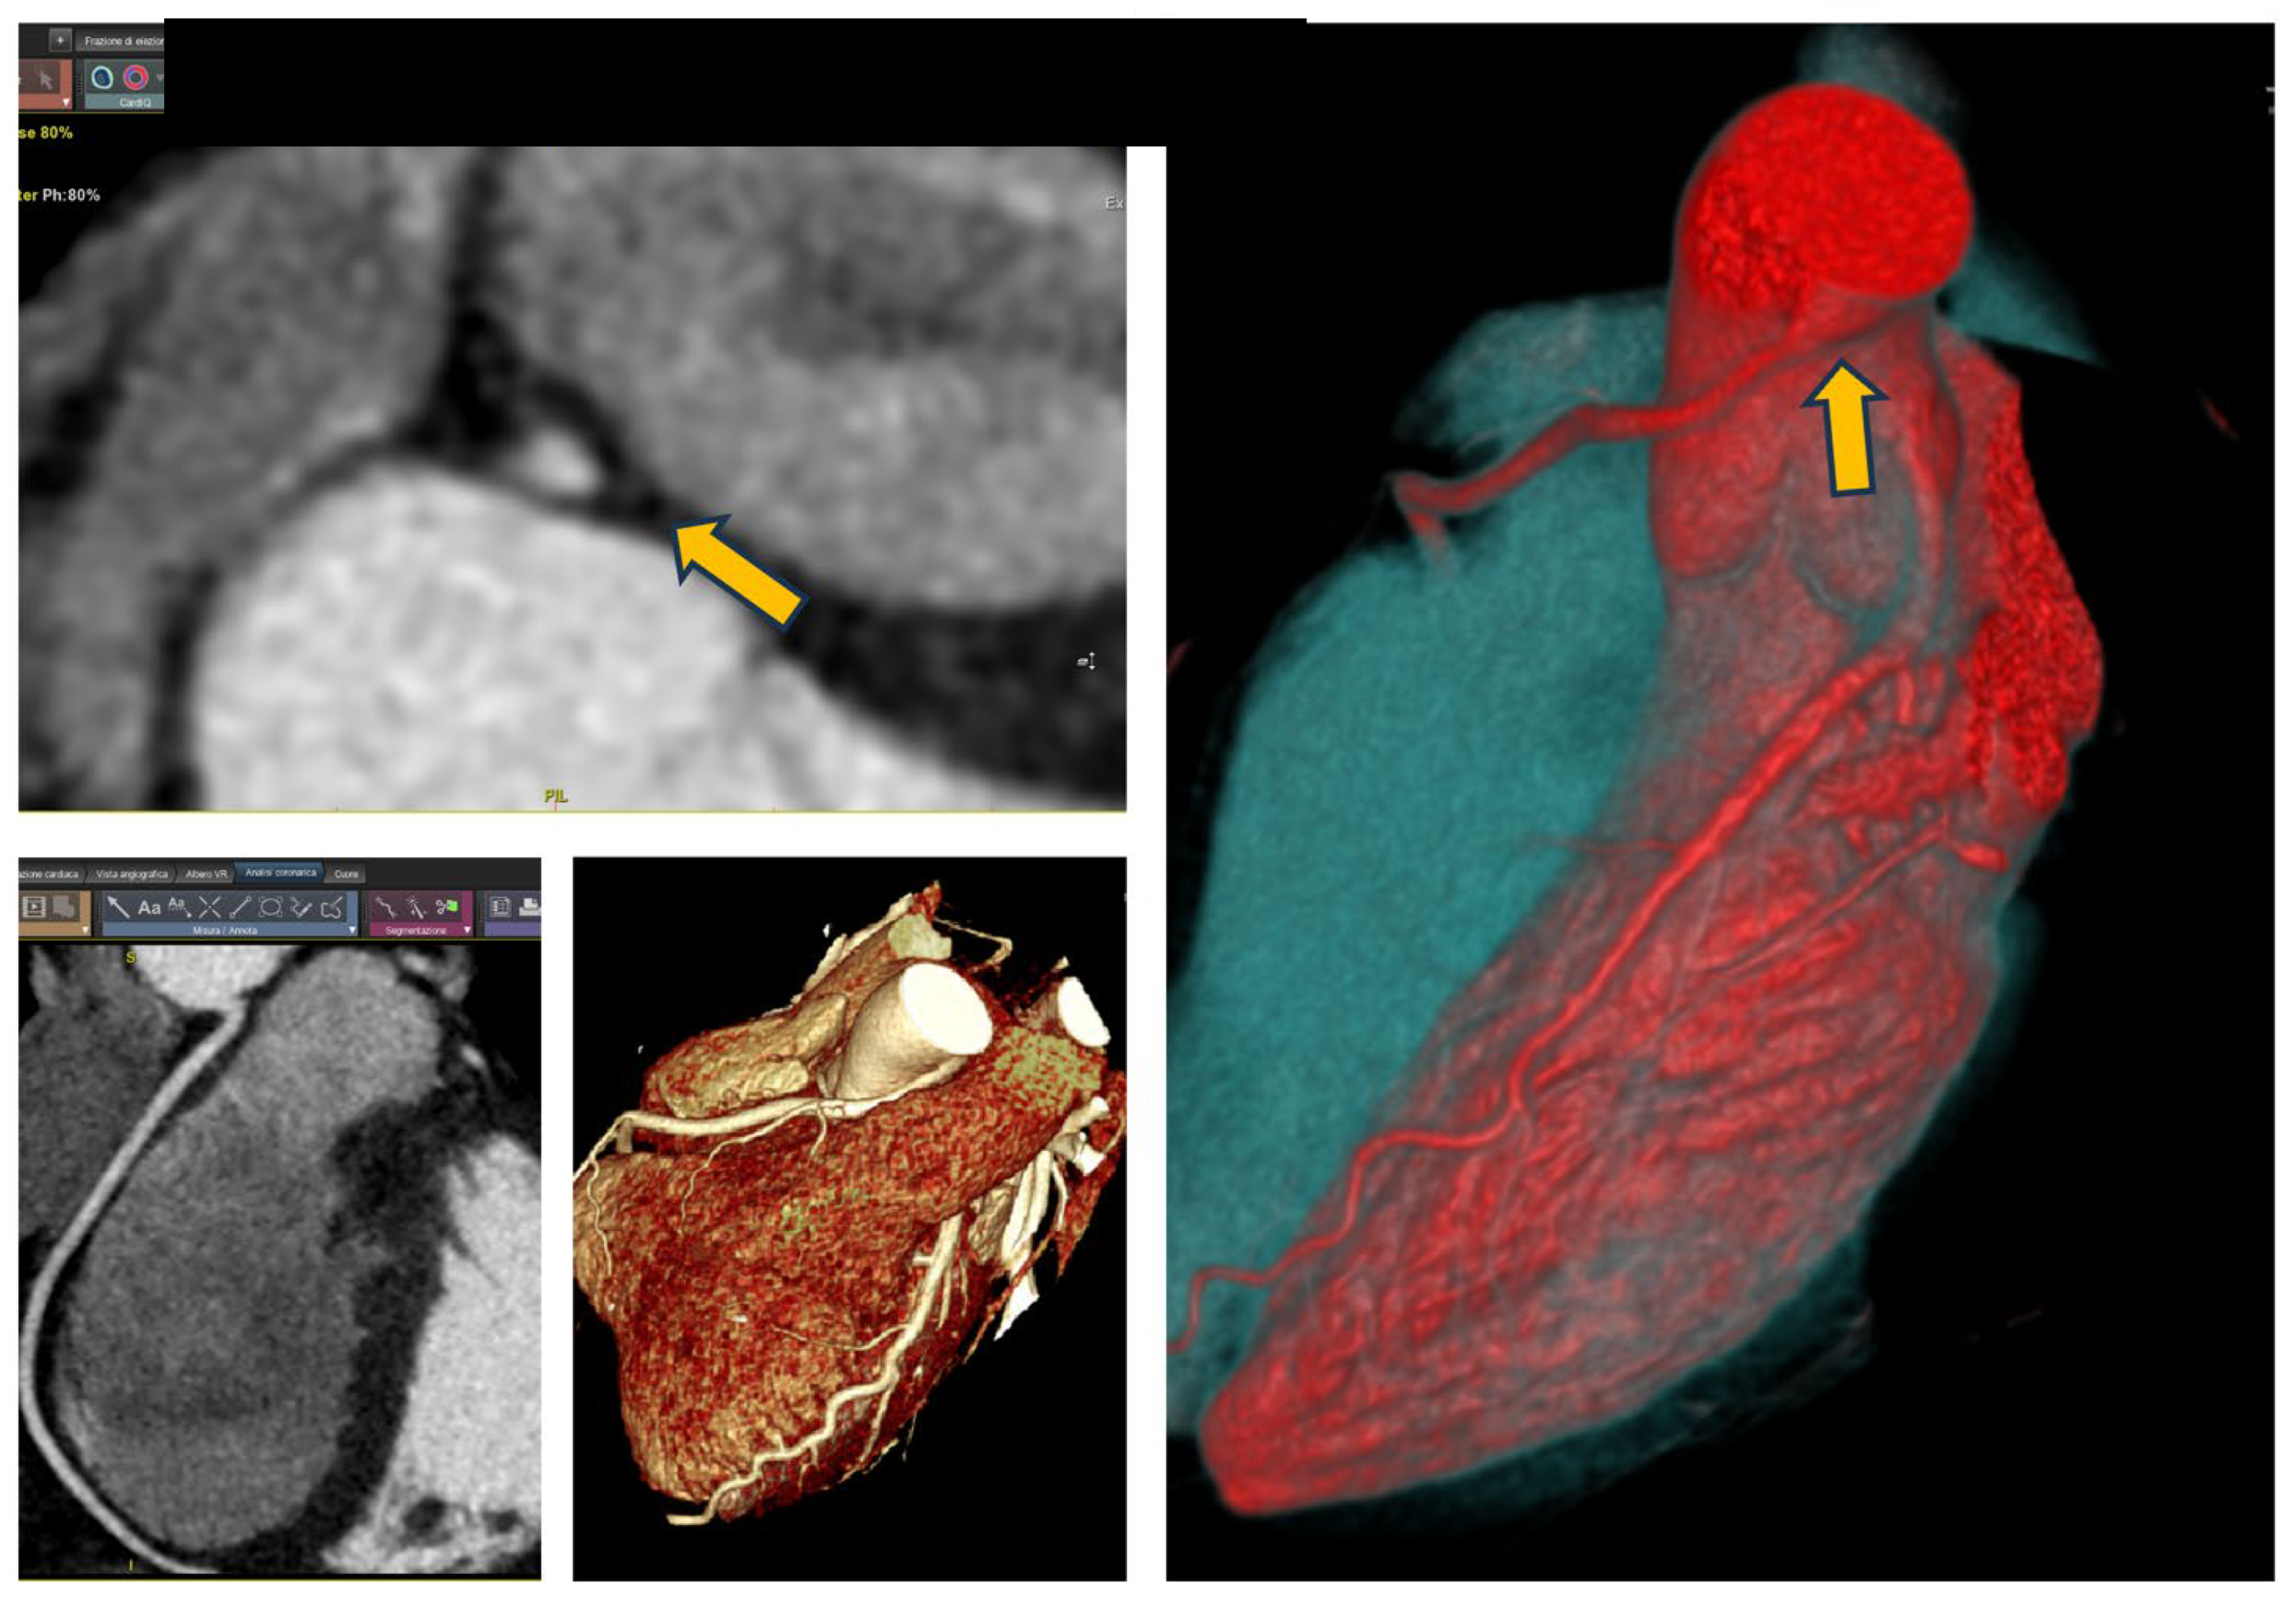

CCTA showed two fistulas originating from two points in the LAD, which, however, do not supply the left ventricle but instead the right ventricle. Furthermore, the fistulous tract does not merely extend to the ventricular wall but opens into the cavity itself, resulting in a shunt condition.

The patient was referred to a tertiary care center, where she underwent a stress CMR with dipyridamole, revealing a significant anterior perfusion deficit. The surgeon opted not to operate, deeming it practically a form of arteriovenous malformation and technically inoperable. The CCTA imagine is shown in Figure 4.

Figure 4. CCTA images of the patient from case 4 with coronary fistula; the two yellow arrows indicate the two points where the fistulous tracts begin, which then give rise to the coronary malformation.